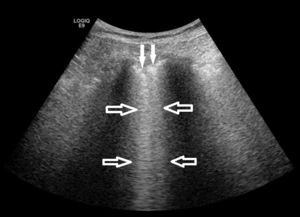

La figura 2 muestra los procesos patológicos en los que los respondedores que realizaban ECOPULM aplicaban la técnica en su práctica clínica. Las aplicaciones más frecuentes fueron la detección de derrame pleural (50% de los respondedores) y la guía de toracocentesis o biopsia pleural (44,70% de los respondedores), mientras que su empleo en las EPID fue sustancialmente menos frecuente (21,22% de los respondedores). Consistente con este último dato, sólo 20 (14,93%) de 134 respondieron afirmativamente a la pregunta sobre si realizaban ECOPULM en las EPID, con los siguientes propósitos: diagnóstico (18; 13,64% de los respondedores), ayuda a decisión terapéutica (9; 6,82% de los respondedores), monitorización de la respuesta terapéutica (7; 5,30% de los respondedores) e investigación (13; 9,85% de los respondedores). La mayoría de los respondedores que realizaban ECOPULM en las EPID evaluaban la presencia de líneas B y las alteraciones de la pleura como marcadores ecográficos del proceso patológico (fig. 3).

Imagen ecográfica del pulmón en una paciente con EPID. Se detectan los artefactos denominados líneas B (flechas huecas) y un engrosamiento irregular de la pleura (flechas sólidas), ambos hallazgos indicativos de las alteraciones alvéolo-intersticiales y pleurales que se producen en las EPIS.